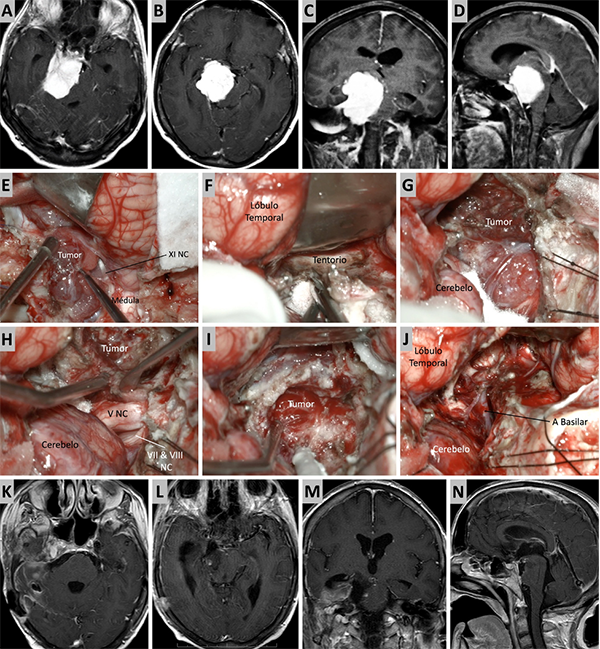

Figura 3. Caso ilustrativo #1. MRPC con implantación petroclival, extensión a la fosa media y compromiso de la incisura tentorial. Paciente con audición conservada. A. Corte axial sobre la región clival media. B. Corte axial sobre la región clival superior. Corte Coronal. D. Corte sagital donde se observa el efecto compresivo sobre el tallo cerebral. E-J. Se realizo un abordaje retrosigmoideo. K-N. Se muestra las imágenes en distintos cortes con el resultado quirúrgico. Residuo tumoral incipiente sobre la incisura tentorial.